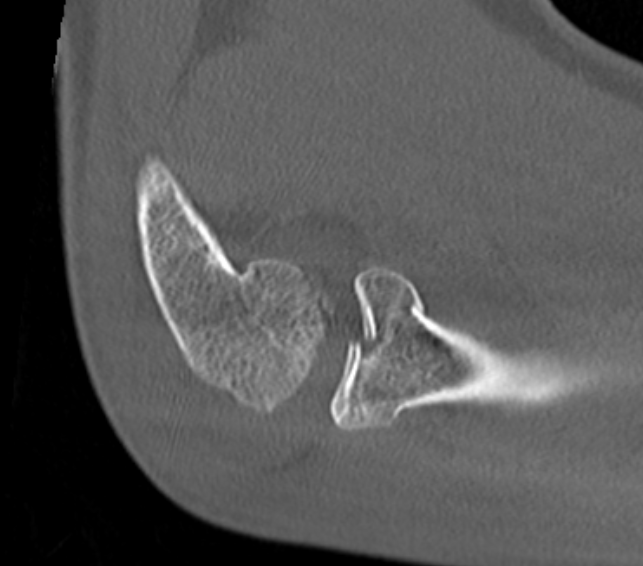

Overstuffing

| Lesser sigmoid notch | Symmetry of ulnohumeral joint |

|---|---|

|

Radial head shoulder articulate with lesser notch

Ensure no gapping of lateral ulnohumeral joint |

- cadaveric study

- increased medial ulno-humeral joint line gapping with overlengthening of 6 or 8 mm

- increased lateral ulno-humeral joint line gapping with overlengthening of 2 mm